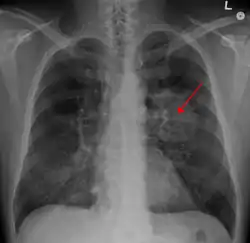

يعدّ التدخين هو السبب الأول لحالات سرطان الرئة حيث يشكل حوالي 85% كسبب رئيسي للإصابة بذلك السرطان وفقط حوالي 10-15٪ من حالات السرطان تحدث عند الأشخاص الذين لم يدخنوا أبدًا.[9][10][11][12] غالبًا ما تنتج هذه الحالات عن مجموعة من العوامل الوراثية مثل التعرض لغاز الرادون، أو الأسبستوس، أو التدخين غير المباشر، أو أشكال أخرى من تلوث الهواء. يمكن رؤية سرطان الرئة على الصور الشعاعية للصدر والتصوير المقطعي المحوسب (CT). يتم تأكيد التشخيص عن طريق الخزعة.[13]

يعتمد تشخيص الإصابة بسرطان الرئة على قيام الطبيب المختص بمجموعة من الفحوصات، ومن هذه الفحوصات والاختبارات ما يأتي:

- الأشعة السينية[7]

- مسح مقطعي (الأشعة المقطعية)[48]